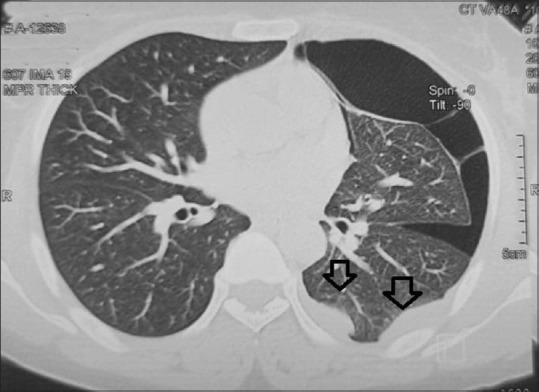

Abstract: Endometriosis is an ectopic implantation of uterine tissue and can affect the thoracic cavity, resulting in Thoracic Endometriosis Syndrome (TES). TES is rare and presents with catamenial pneumothorax, haemothorax, and hemoptysis, often coinciding with menstruation. We report a case of a 46-year-old female with a decade-long history of hemoptysis and periodic chest pain associated with her menstrual cycle. High-resolution CT scans revealed persistent pneumothorax and pleural nodules. A dry thoracoscopy was performed, and biopsies confirmed the diagnosis of TES through histopathology and immunohistochemistry. This case highlights the importance of considering TES in women with cyclic respiratory symptoms and demonstrates the diagnostic value of dry thoracoscopy in benign conditions of the pleura. Raising awareness among clinicians is crucial for timely diagnosis and management of TES, reducing patient morbidity.